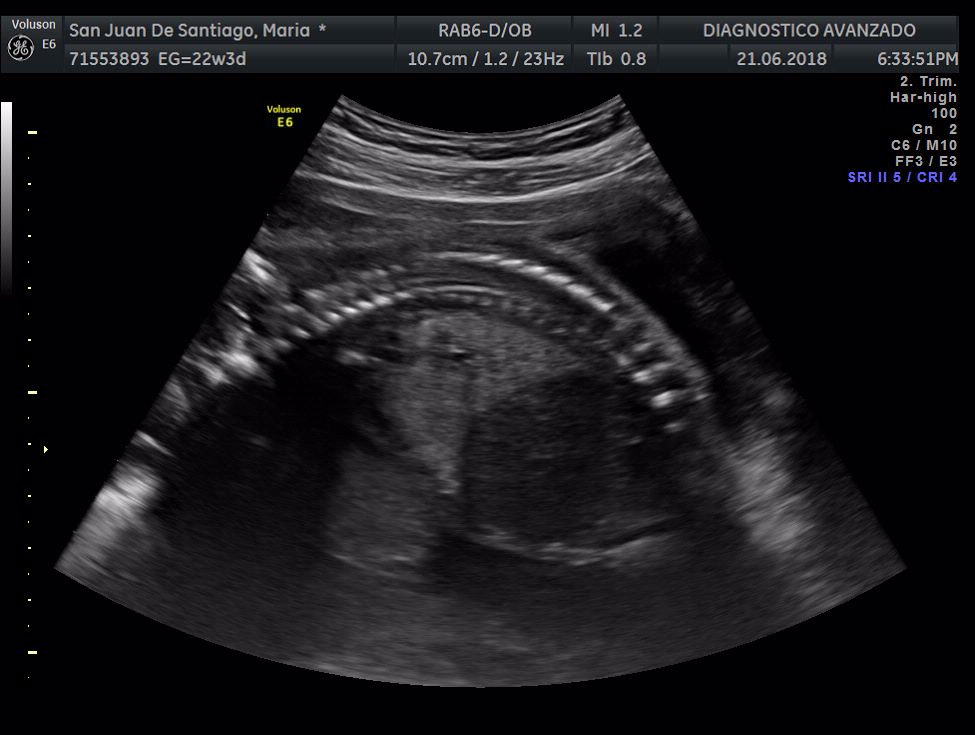

¡Hola a todos! Hoy hemos ido a hacer la tradicional ecografía 3D de la niña, os dejamos todo el material (aunque es un poco demasiado).